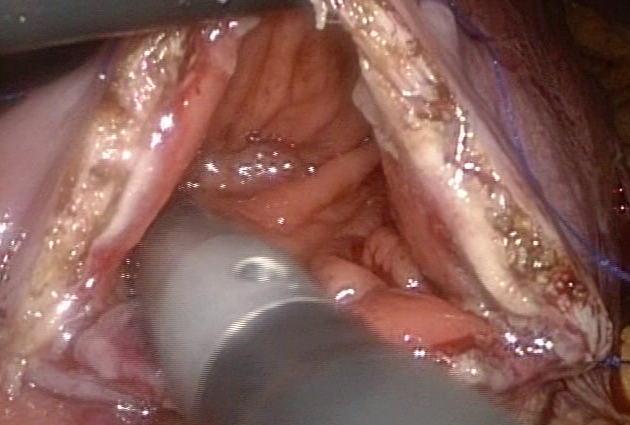

- Liver resection (for cancer and other liver tumor)

- Distal pancreatectomy (for removal of pancreas tumor)

- Whipple operation (for removal of pancreas cancer)